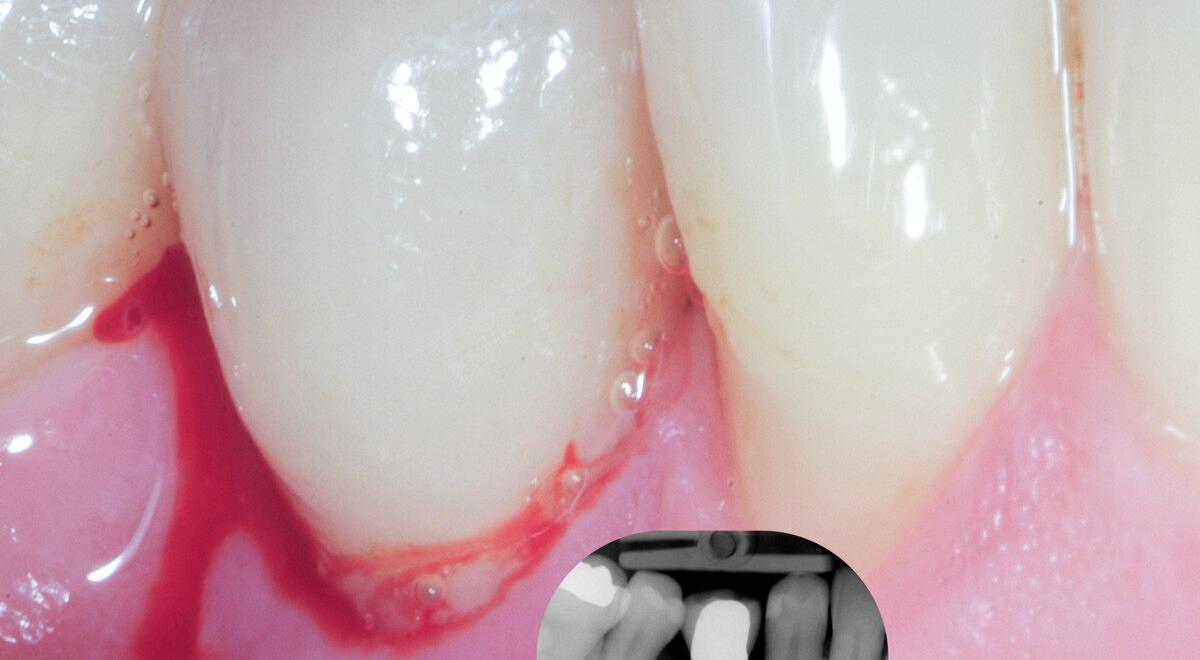

Peri-implantaire ontstekingen, zoals peri-implantaire mucositis en peri-implantitis, vormen een belangrijke bedreiging voor het behoud van tandimplantaten. Deze multifactoriële aandoeningen ontstaan door de interactie tussen bacteriële biofilm, materiaaleigenschappen van het implantaat en de immuunrespons van de gastheer. Risicofactoren als slechte mondhygiëne, parodontitis in de voorgeschiedenis, systemische aandoeningen en iatrogene factoren spelen hierbij een cruciale rol. In deze nascholing leert u hoe u deze ontstekingen tijdig herkent, voorkomt en behandelt. Blok A behandelt de risicofactoren, preventieve maatregelen en het belang van een goed ontwerp van de prothetische constructie. Blok B gaat in op diagnostiek en behandeling: van het meten van pocketdiepte tot het inzetten van niet-chirurgische reiniging, eventueel gevolgd door een chirurgische aanpak bij peri-implantitis. U krijgt inzicht in een stapsgewijze behandelstrategie, met nadruk op vroege detectie en het belang van een gestructureerd nazorgprogramma. Na afloop van deze e-learning bent u beter toegerust om peri-implantaire ontstekingen effectief te voorkomen en behandelen, met als doel het behoud van implantaten op de lange termijn.